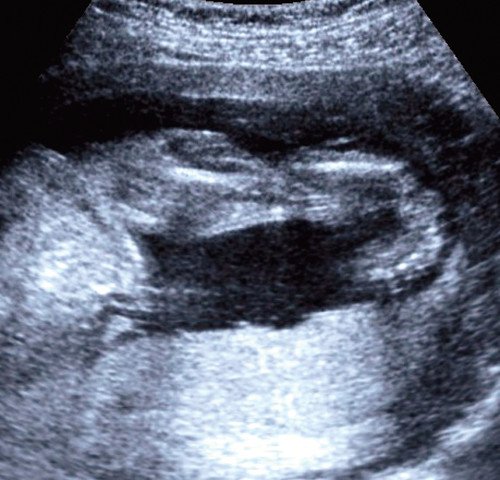

При эхографии нами было выявлено отсутствие каких-либо отклонений от нормативных показателей анатомии плода (торакоабдоминальный индекс составил 0,93) за исключением обеих нижних конечностей. Длина бедренных, плечевых костей, костей предплечий соответствовала гестационному нормативу. Изменений их формы, строения также не установлено. Малоберцовые кости укорочены: правая - 22 мм, левая - 26 мм. Большеберцовые кости: правая - 8 мм, левая - 12 мм. Правая большеберцовая кость искривлена (рис. 1).

Отмечалась полидактилия в сочетании с синдактилией обеих стоп (рис. 2). Обе стопы были ротированы: отмечалась варусная девиация справа, вальгусная - слева (рис. 3, 4). В режиме поверхностной реконструкции ультразвуковые "находки" получили свое подтверждение (рис. 5).